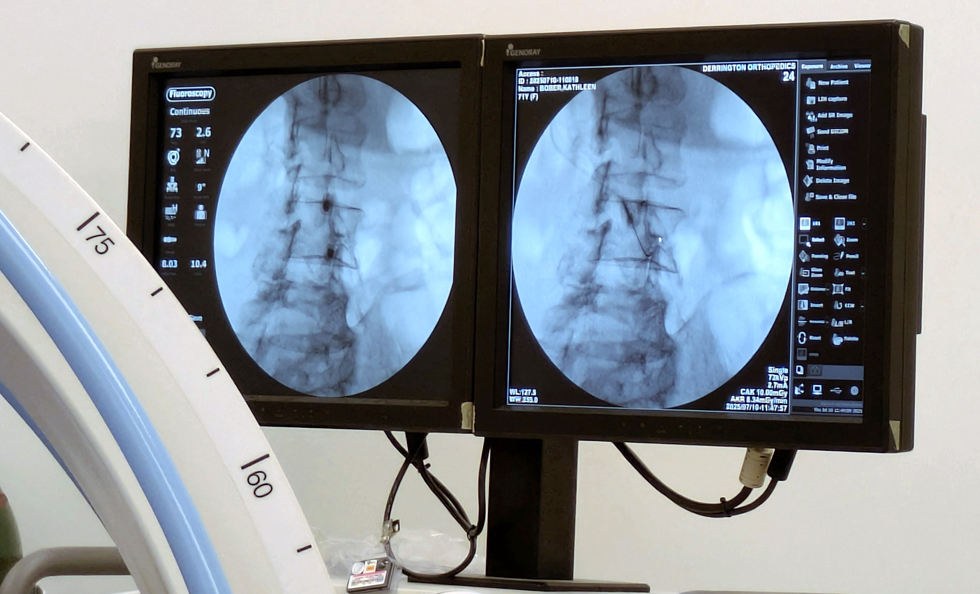

On Thursday, July 10, I had the PRP treatment done on my hip and lumbar spine. Again, blood was drawn first and then processed to isolate and concentrate the platelets, which were then injected back into me. This process aims to harness the healing properties of platelets, which contain growth factors that can promote tissue repair and regeneration.